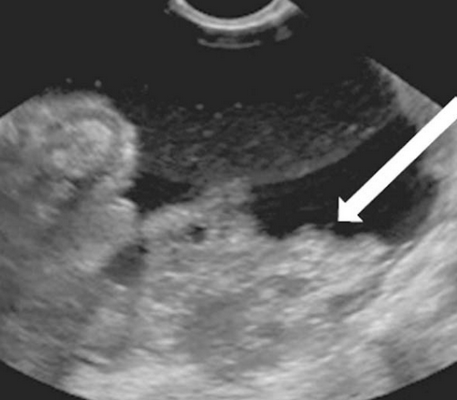

Рис. 6. Метастазы рака молочной железы: гиперэхогенный карциноматоз в малом тазу (стрелка).

Метастазы рака молочной железы были наиболее часто присутствующими в виде гиперэхогенного карциноматоза с асцитом. У четырех из шести (66,7%) был только карциноматоз и не было тазовой опухоли. Карциноматозные очаги были гиперэхогенными (в отличие от карциноматозных очагов первичного эпителиального рака яичников) (рис 6).